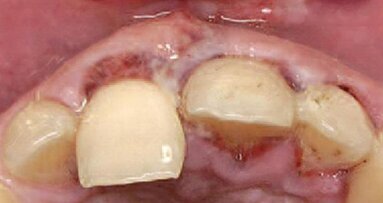

Materiał badawczy stanowiło 46 pacjentów (25 kobiet i 21 mężczyzn) w wieku 30-71 lat leczonych w Zakładzie Chirurgii Stomatologicznej Warszawskiego Uniwersytetu Medycznego w latach 2010-2013, u których występował brak przynajmniej jednego zęba kwalifikujący się do leczenia implantologicznego i jednocześnie przynajmniej jeden ząb wymagający leczenia endodontycznego.

Leczenie endodontyczne przeprowadzono metodą step-back. Kanały wypełniano metodą kondensacji bocznej gutaperki, jako uszczelniacz stosowano pastę AH26 (Dentsply). W celu odbudowy braku zęba stosowano implanty SPI firmy Alpha Bio. Są to implanty charakteryzujące się jedną z wyższych stabilizacji pierwotnych wśród systemów implantologicznych. Kształt nadający właściwości samonawiercające umożliwia zmianę pozycji w trakcie wprowadzania i ukierunkowanie implantu.

Po przeprowadzeniu leczenia implantologicznego i endodontycznego oceniano parametry kliniczne wokół zębów leczonych endodontycznie i implantów. W celu tej oceny stosowano zmodyfikowany na potrzeby badania indeks PES (Tab.1). Badanie kliniczne obejmowało ocenę estetyki tkanek miękkich oraz głębokości kieszonek przyzębnych zęba leczonego endodontycznie oraz implantu. Pomiary przeprowadzano bezpośrednio po zacementowaniu pracy długoczasowej na implancie, tzn. po 6 miesiącach od jego wprowadzenia. W tym samym czasie przeprowadzano badanie kliniczne zębów leczonych endodontycznie. Kolejny raz ocenę kliniczną przeprowadzano po 12 miesiącach od rozpoczęcia leczenia.

Autor prezentuje przypadek ekstrakcji z wczesną implantacją i jednoczasowym przeszczepem kości i tkanek miękkich.